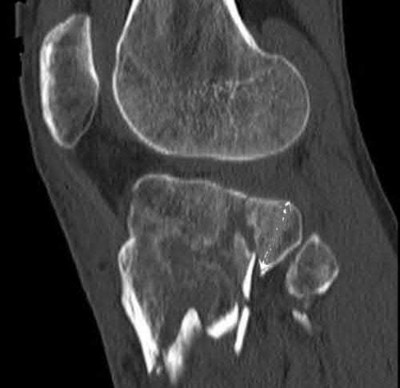

The radiograph shows a comminuted pilon fracture, which is associated with high-energy trauma and significant soft tissue injury. The tested concept here is the importance of avoiding definitive reduction and fixation of this high-energy injury, which has been shown to be associated with an increased risk of wound complications and deep infections (as compared to staged treatment with usage of a spanning external fixator).

Patterson et al. reviewed 23 consecutive patients with comminuted distal tibia fractures. They showed 0% infections or wound-healing problems in their patient population treated with a two-staged protocol. Their protocol involved fibula fixation with an intramedullary implant and application of a medial external fixator to to regain length and restore anatomic alignment. Reevaluation of the limb occurred ten to fourteen days later for definitive fixation.

Sirkin et al. retrospectively reviewed 40 closed and 17 open pilon fractures (AO types 43A-C) that were treated with staged surgical management (avg. time from ext. fix. to formal reconstruction was 14 days (range 4 to 31) They reported 17% post-operative wound complication in the closed group and 11% post-operative wound complication in the open group (Gustilo Type I-III). They suggest the technique was successful in both closed and open pilon fractures.

A 34-year-old male sustains the closed injury seen in Figure A as a result of a high-speed motor vehicle collision. What is the most appropriate next step in treatment?